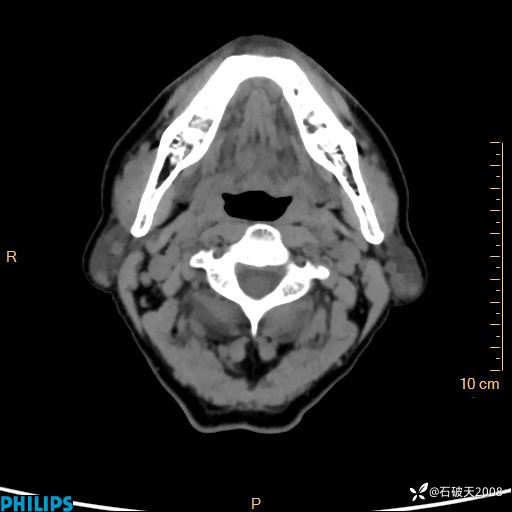

动脉期